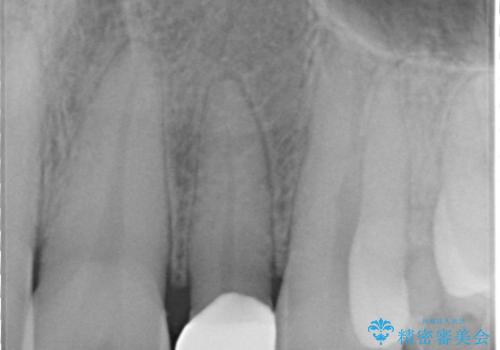

- 矯正治療で配列した矮小歯をオールセラミッククラウンで修復治療を行いました。

オールセラミッククラウンは、隣の歯に合わせて色調を調整することができるため非常に綺麗に仕上がります。